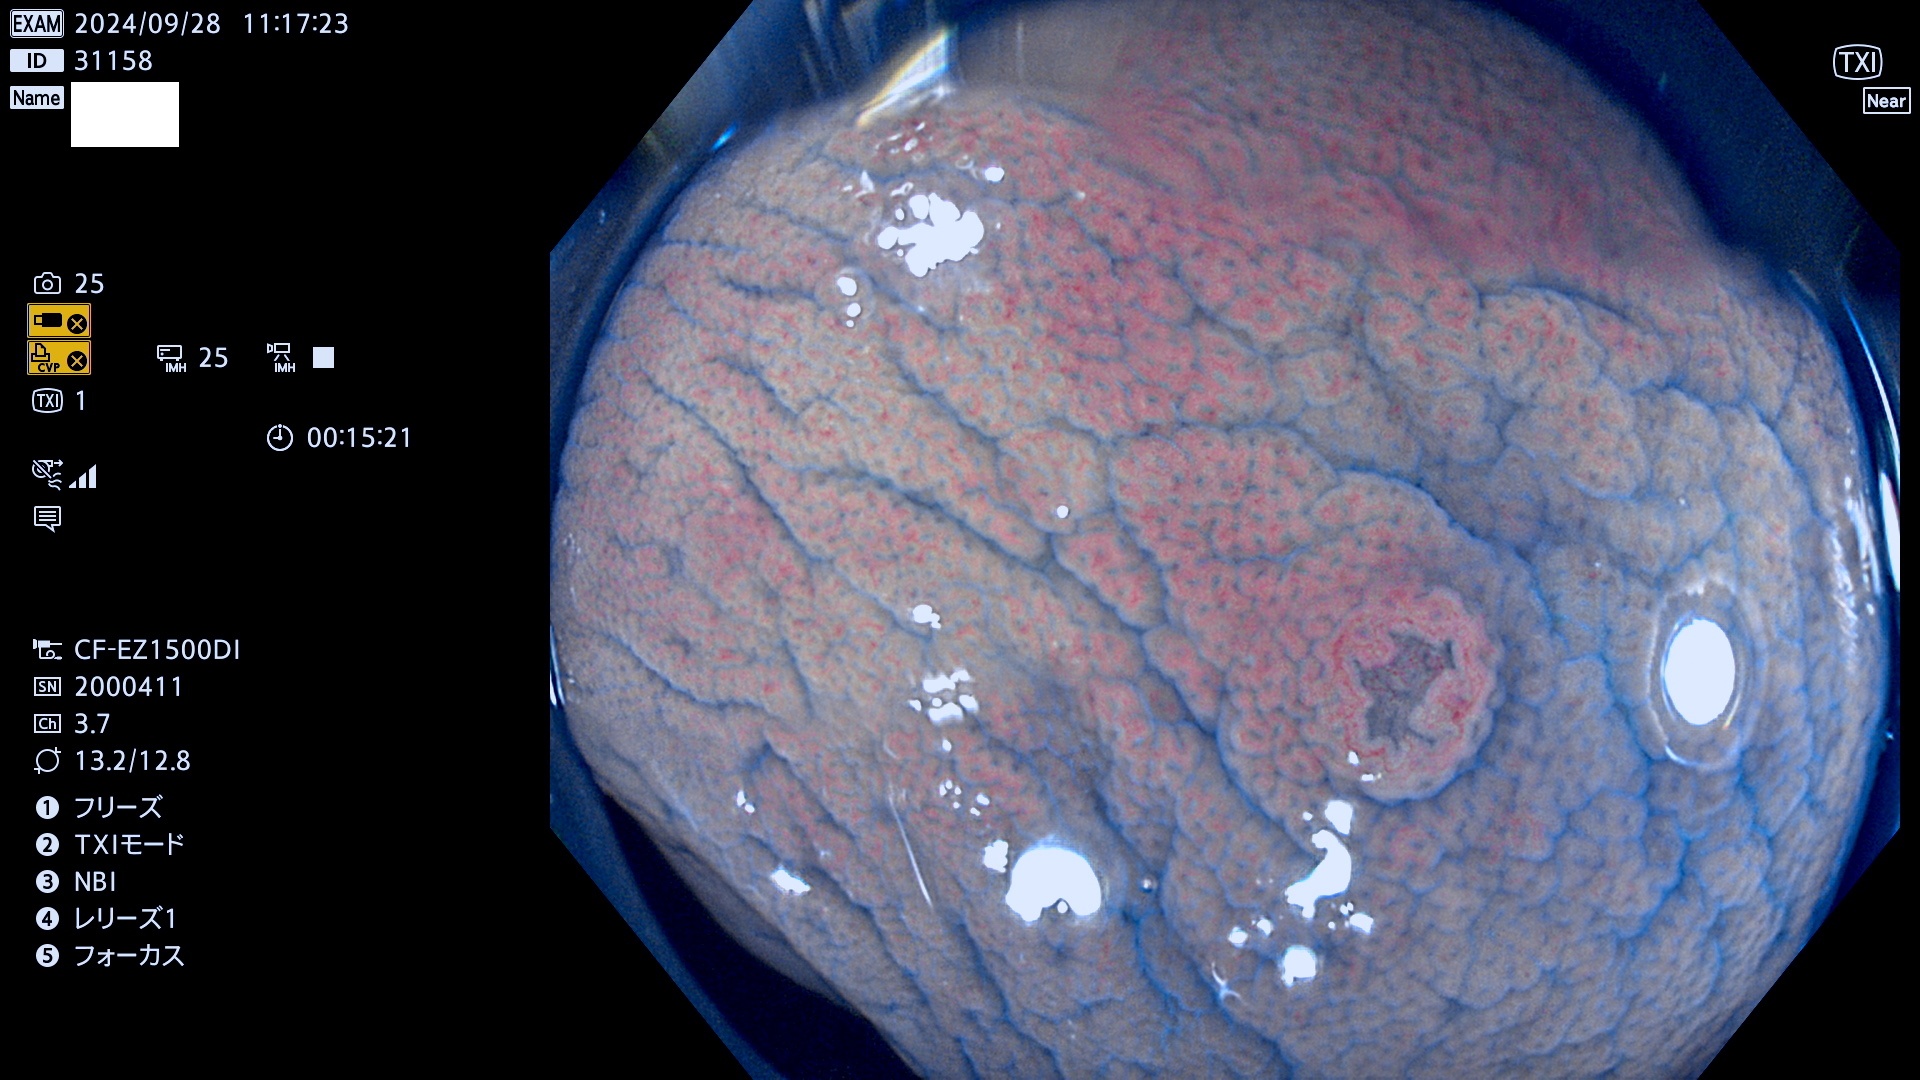

今週のUb、Uc型腺腫

完全に平坦な物をUb、陥凹している物をUcと呼びます。最も発見が難しく危険な病変です。

毎週の検査(木・金・土・日)に発見されたUb、Uc型・腺腫を、その週の日曜の夜にUPし1週間、提示します。

抽出の対象期間 2024年9月26日〜9月29日の4日間(48件の検査)12件 (12/48=25%)